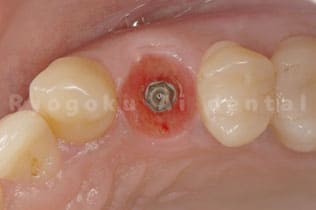

STEP 4

- インプラント治療開始

- 骨の状態や歯の割れている状態によって、先に歯を抜いてからインプラント治療を行う場合と、抜歯と同時にインプラント治療を行う場合の2種類あります。

STEP 6

- 型取り

- インプラントが問題なく骨と付いているのを確認できたら型取りを行います。

STEP 7

- インプラント治療終了

- 最終的な被せ物をセットして終わりとなります。その後はインプラントが長持ちするようにメンテナンスを定期的におこないます。